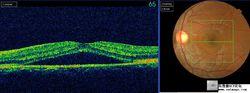

眼底鏡、眼底相機、OCT、造影

其中OCT是目前眼底檢查比較常用的,它既可定性也可定量的對病變進行分析診斷。

④眼底改變:檢眼鏡檢查可見黃斑部有約1~3PD大小、邊界清楚的盤狀漿液性神經上皮脫離區。脫離區色較暗,周圍有反光暈,中心凹反光消失。發病數周后脫離區視網膜可見多數散在的黃白色小點沉著。恢復期視網膜下積液吸收,中心凹反光恢復,但仍可殘留有光澤的陳舊性黃白小點和輕度色素紊亂。

⑤眼底血管螢光造影所見:在動脈期或靜脈早期,黃斑區出現一個或數個高螢光滲漏點,以後隨著時間的推移,滲漏點逐漸擴大增強。伴有色素上皮漿液性脫離時,在動脈早期就有螢光勾畫出色素上皮漿液性脫離的範圍,隨著造影過程逐漸增強其亮度持續到後期,但其大小、形態始終不變,當正常脈絡膜螢光消退後仍清晰可見。色素上皮脫失的陳舊性病變,造影時可見窗樣缺損的高螢光。